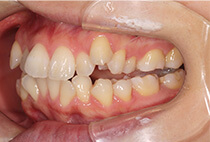

治療後

そのため、かみ合わせと顎関節症の治療を同時に行ったにもかかわらず、2年間で治療が終了。

かみ合わせが整い咬筋の過緊張も改善しました。咬筋の肥大も治ってフェイスラインがすっきりしました。

最終的には美しい歯並びと、安定した痛みのないかみ合わせが実現しました。

しっかり前歯を下げるために、インプラントアンカーを使用してコントロールしました。